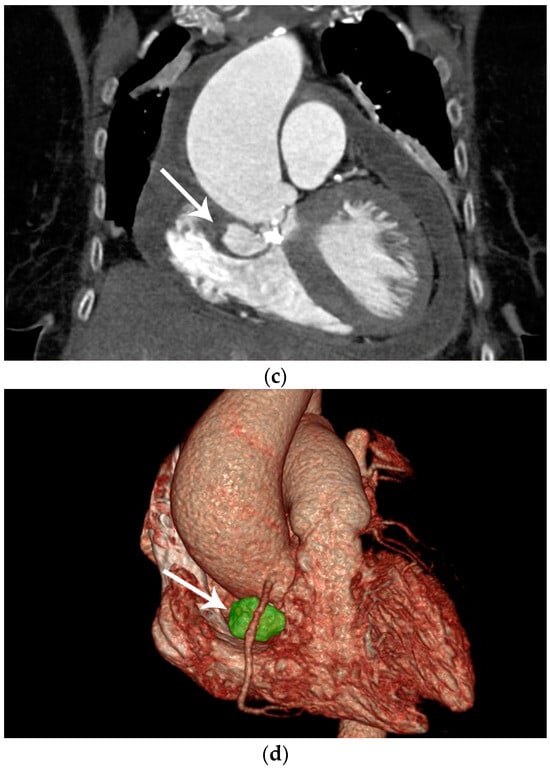

Figure 1. Preoperative diagnostic imaging of an 83-year-old female patient presenting with progressive symptomatic aortic valve stenosis. (a) Preoperative laevocardiography showed a para-aortic contrast media deposition. The cavity showed a wide base and was in continuity with the left ventricle. In this case, the initial diagnosis was made during standard laevocardiography. This allows for direct identification of the primary entry site and connection of the cavity, which is an important factor during differential diagnosis. If the initial diagnosis is made with other modalities such as echocardiography, the entity and connection of pericardiac and periaortic lesions may be more difficult. As an example, Emmert et al. reported a case of a chronic subannular abscess that was misdiagnosed for a sinus of Valsalva aneurysm and was only diagnosed correctly during intraoperative exploration [1]. Thus, live transcatheter contrast imaging as performed here can help to avoid incorrect preoperative diagnosis and preparation. In this case, preoperative echocardiography remained inconclusive with respect to the suspected lesion, although transthoracic or transesophageal echocardiography is widely accepted as the primary imaging method for infectious cardiac diseases [2,3]. In this selected patient group, in which the topographic anatomy remains unclear in other imaging modalities, laevocardiography may provide critical additional information for planning of the procedure. However, the risk of embolization associated with catheterization must be taken into account, particularly in the case of larger vegetations. (b) To confirm the initial preliminary diagnosis, contrast-enhanced computed tomography was utilized. Computed tomography, or cardiac magnetic resonance imaging, has increasingly become the gold standard for the imaging of more complex complications of infective cardiac diseases [4]. The main advantage of this imaging technique is the three-dimensional visualization of the cavity dimensions and connections. For this, electrocardiographic gating during computed tomography is recommended to avoid artifacts. In this horizontal plane of the computed tomography imaging of our patient, the wall of the spurious aneurysm was thickened (arrow), which may correspond to partial mural thrombosis or post-infective morphologic changes. In this context is should be considered that aortic subannular abscess-like formations can arise not only from infective endocarditis, but may also result from non-infective inflammatory lesions such as Libman–Sacks endocarditis, as reviewed by Murillo et al. [4]. Additionally, left ventricular hypertrophy, pericardial effusion, and pleural effusion were apparent in computed tomography imaging, indicating the beginning of cardiac decompensation. (c) In the frontal plane, the connection of the abscess cavity to the left ventricular outflow tract was visualized. Heavy calcification not only of the aortic valve but also of the base of the pseudoaneurysm was noted. Additionally, the aneurysmatic dilatation of the ascending aorta, which most likely resulted from the chronic aortic stenosis as a poststenotic aneurysm, can be seen in this plane. In prior studies, this poststenotic dilatation has been described for aortic stenosis, especially when the aortic valve is bicuspid [5]. (d) Three-dimensional reconstruction of the suspected lesions may be of great interest for operative planning, since this technique allows for the visualization of the local topography of the target lesion. In this case, the close topographic proximity of the abscess excavation to the right coronary artery became apparent (arrow). With ever improving rendering and electrocardiographic gating techniques, contrast-enhanced computed tomography has evolved into a powerful diagnostic tool in the preoperative planning for complex cardiac malformations [6].